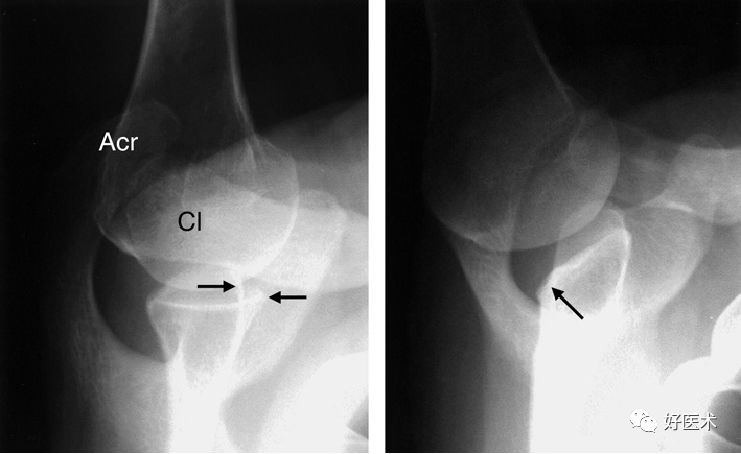

CT显示肩关节不稳

后脱位:反Hill-Sachs损伤

后关节盂撕脱小骨折